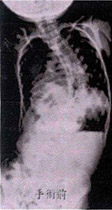

平成19年2月13日

60度で来院

レントゲン平成19年2月13日

�@平成19年 2月装具 無 60度